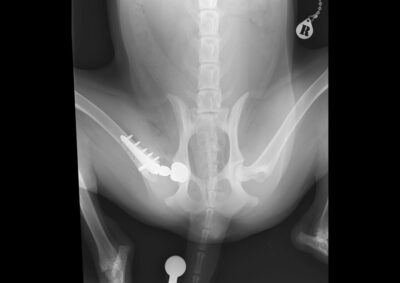

注意 ボタンをクリックした先に、治療中および手術中の画像が説明で使用されている場合がございます。 そのような画像に弱い方は閲覧なさらないようお願いいたします。 整形外科 若齢犬の橈骨固定術 #271 整形外科 前十字靭帯断裂(中型犬)に対するCBLO #255 整形外科 超小型犬に対する上腕骨遠位Y字骨折 整形外科 大型犬の前十字靭帯疾患(慢性経過)に対するCBLO #254 整形外科 橈骨固定術 #270 整形外科 膝蓋骨内方脱臼に対する人工滑車置換術 PGR #23 整形外科 犬の前十字靭帯(疾患)部分断裂に対するCBLO #253 整形外科 犬の前十字靭帯断裂に対するCBLO #252 整形外科 膝蓋骨内方脱臼+前十字靭帯断裂に対するPGR#22・LSS 整形外科 大腿骨骨折 整形外科 橈骨固定術 #269 整形外科 上腕骨外顆骨折の癒合不全 123456> 症例カテゴリー 放射線治療整形外科軟部組織外科脳神経外科内科腫瘍外科救急・集中治療リハビリテーション科腫瘍内科内視鏡科脳神経科呼吸器外科中医・漢方猫の腎移植循環器科